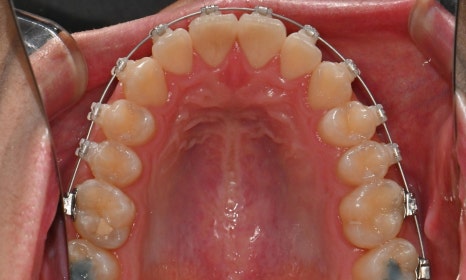

2026.1. 치료 종료 - 연세정원치과

약 1년 간의 교정 치료를 통해 어긋나 있던 치아 중심선이 자연스럽게 맞춰졌고, 중심선 비대칭이 개선 및 하악 아랫입술 돌출도 눈에 띄게 호전되었습니다. 무엇보다 치료 기간 동안 앞니의 치근 흡수는 추가적인 진행 없이 안정적으로 유지되었습니다.

돌출을 조금 더 개선하는 것을 추천했으나, 환자가 갑자기 군 입대를 하게 되어 현 상태로 치료를 마무리하기로 하였습니다. 치료 전후 치아 위아래 중심선이 일치하며 좌우 어금니 교합도 향상되었습니다. 하악 치열의 후방 이동으로 아래 입술의 돌출도도 많이 개선되었습니다. 멀리서도 믿고 내원해주고, 치료 기간 동안 성실히 협조해준 환자분께 감사드리며 앞으로도 건강한 치아로 군 생활 잘 마치길 응원합니다 :)